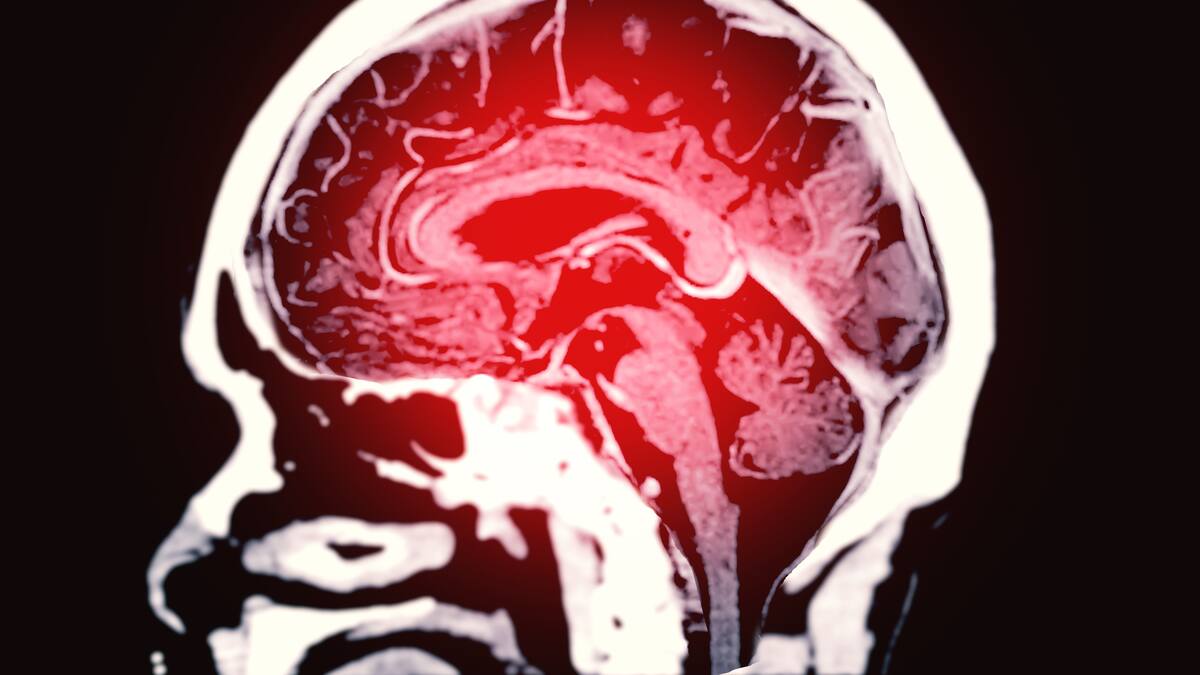

¿Hay forma de saber si se es propenso a sufrir un ACV? Neurólogo explica

Los accidentes cerebrovasculares son una trombosis cerebral en donde se forma un trombo o se da una hemorragia de manera súbita.